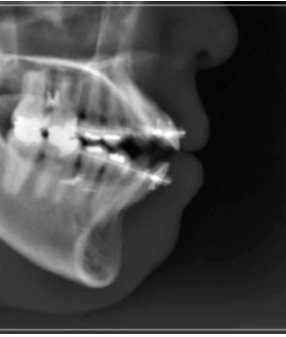

만일 이러한 개방교합이 턱관절 질환에

의해 발생하였을 경우 잘 모르고

치아 교정부터 진행하게 되면

턱이 불안정한 상태에서 무리하게

치아를 이동시키게 되기 때문에

오히려 질환을 악화시키거나

개방교합이 다시 재발하는 등 문제가

발생할 수 있어 주의가 필요했어요.

또한, 겉으로는 개방교합이 없는 것처럼

보여도 턱관절 질환을 앓고 있다면

숨겨져 있을 수 있으므로 평소